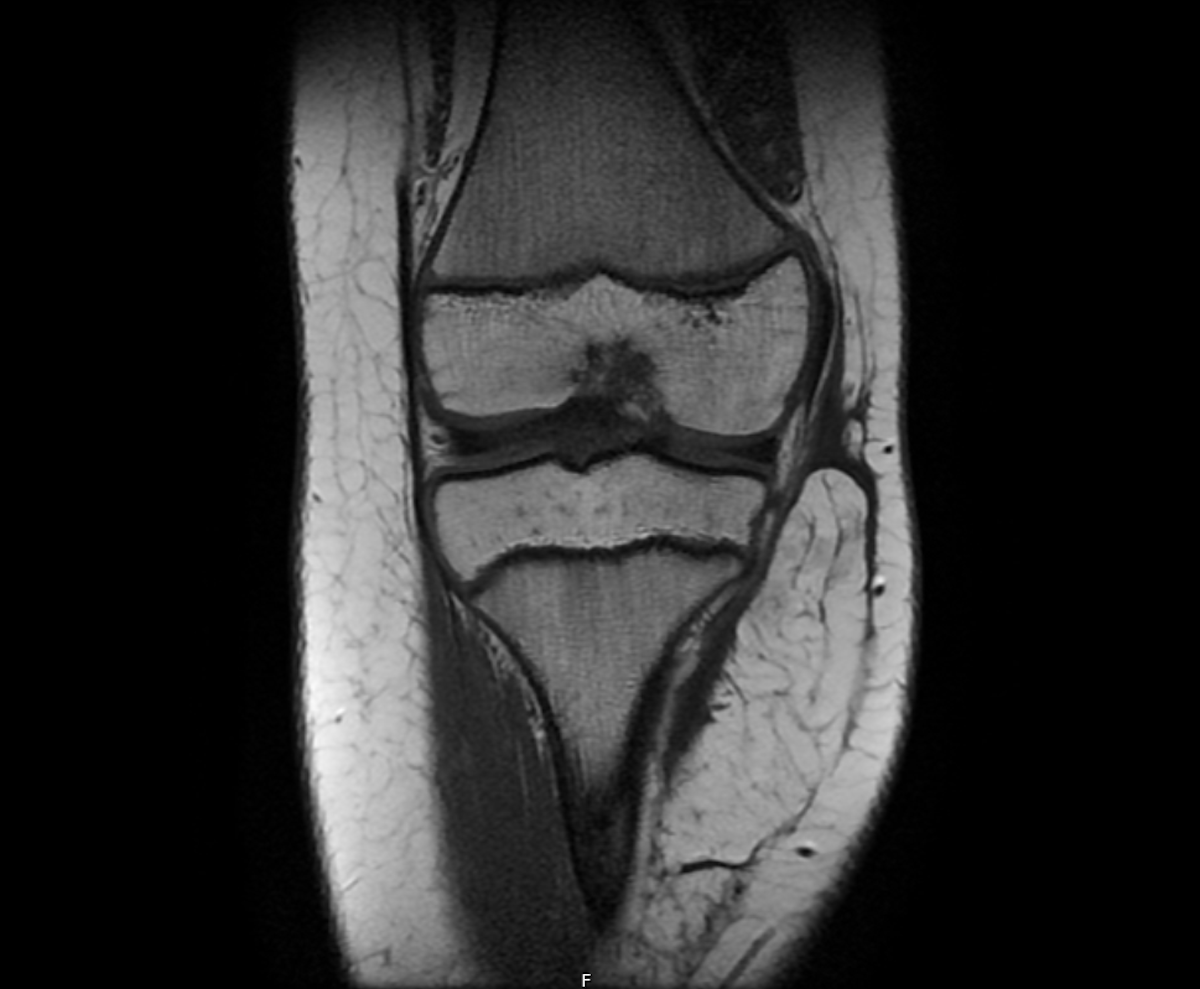

Fig. 3. RM de la lesión en plano frontal.